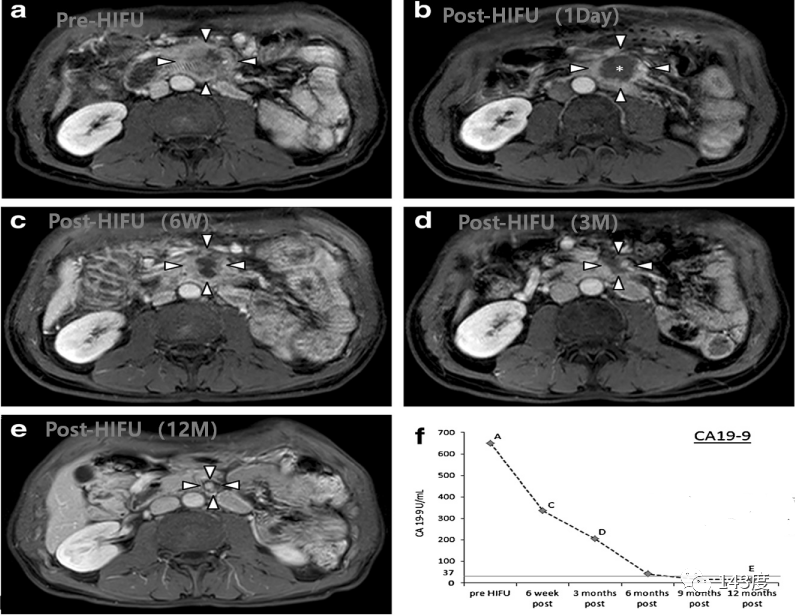

Pancreatic Cancer Treatment Case 3:

Patient: Male, 54 years old, pancreatic cancer

Pain completely relieved within 2 days after HIFU (high-intensity focused ultrasound) treatment. The tumor shrank by 62.6% at 6 weeks, 90.1% at 3 months, and CA199 levels returned to normal at 12 months.